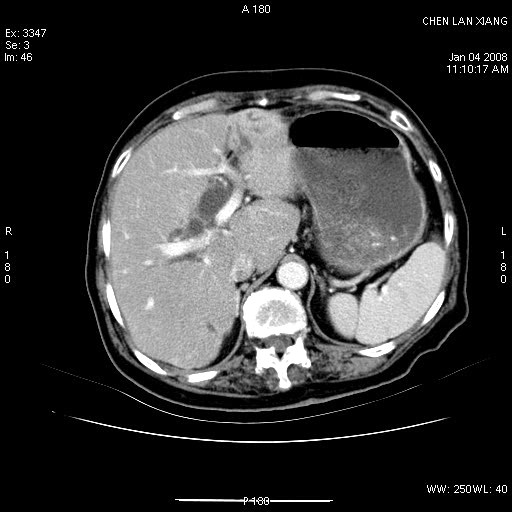

女,76岁,腹痛3-4天,b超示:肝内实性肿物,胆囊强回声,胆总管扩张.

考虑:1、胆总管下端结石伴梗阻性肝内外胆管扩张(肝左叶外侧段肝内胆管多发结石、胆管炎);

2、肿囊癌累及肝,不除外 黄色肉芽肿性胆囊炎。

1 胆总管末端结石伴肝内胆管结石,肝内外胆管扩张。2 胆囊扩大,胆囊壁不规则增厚,内见软组织密度影。考虑:慢性胆囊炎,不除外胆囊癌!

标题: 肝右叶病灶

胆囊癌侵犯肝右叶?

1)胆囊癌伴肝脏转移。2)胆总管下端结石、肝内胆管结石伴肝内外胆管扩张。